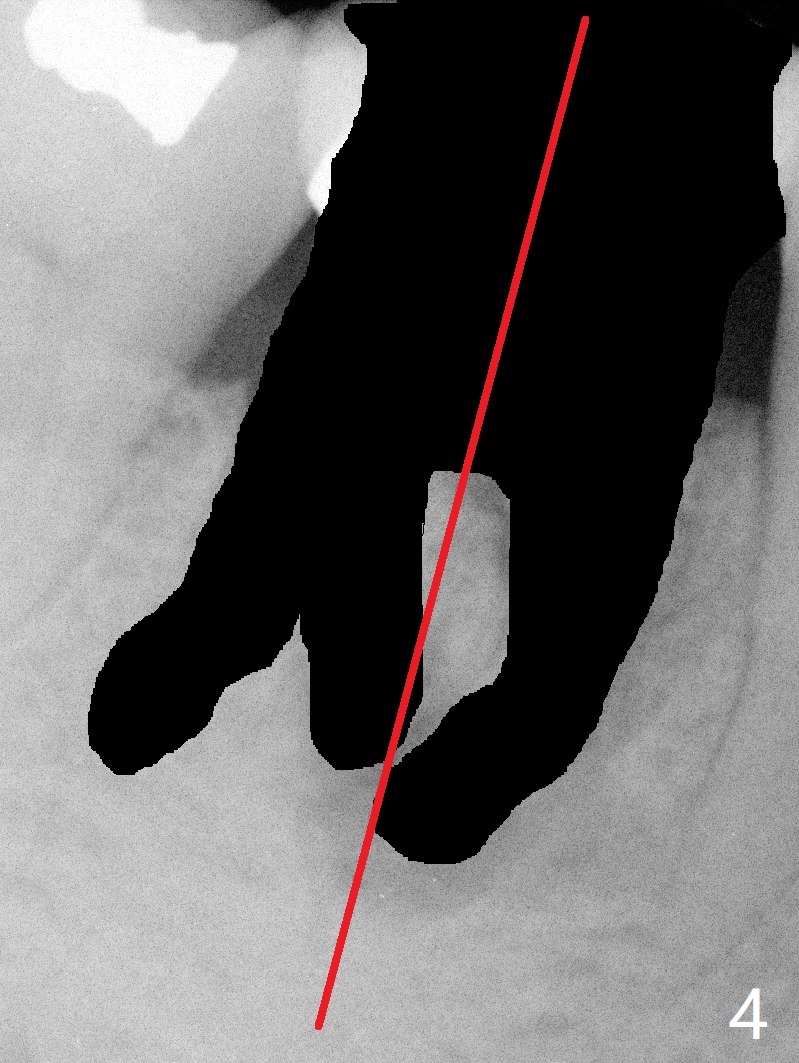

A 55-year-old woman has severe bone loss (Fig.1 with buccal and lingual fistulae) around the mesial (M in Fig.2) and distolingual (DL) roots. If there is a septum after extraction (Fig.3 S), osteotomy will be established in the septum to enhance primary stability (Fig.4). When the septum cannot be saved (Fig.5), osteotomy is to be initiated in the septal slope oblique (Fig.6 <). The osteotomy will be straightened once an entry is made (Fig.7). The initial osteotomy is slightly distal, since as osteotomy increases (Fig.8 blue), it tends to shift mesial (arrow). In addition, the apex of the 2nd bicuspid tilts distal (yellow dashed line). Depth of osteotomy is 20 mm (crest, Fig.9) or 18 mm (septum) so that 8 mm of the native bone can be obtained with 3 mm clearance from the Inferior Alveolar Canal (red dashed line). PRFx2 is required (seems not done).